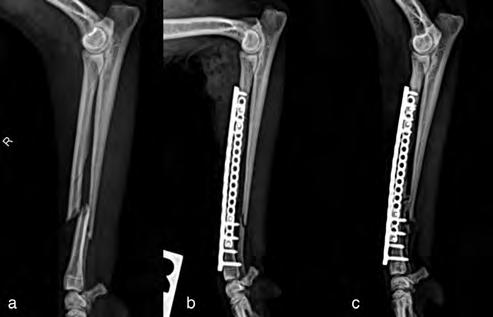

Después de la cirugía se analizaron las radiografías postoperatorias, realizándose las mismas mediciones que en la planificación, y observándose cómo los valores obtenidos tras la cirugía se correspondían con los valores planificados (Fig. 5). Se colocó un vendaje postoperatorio sencillo durante 14 días, para evitar la manipulación del área quirúrgica por parte de la pa-

ciente, lo que facilitó una cicatrización correcta de la herida y una buena recuperación del animal, que comenzó a caminar con normalidad a los pocos días de la intervención (Fig. 6).

En cuanto a la evolución, resulta vital realizar radiografías de seguimiento postoperatorio con cierta periodicidad (Fig. 7). Esto nos permite tener un control adecuado del animal y actuar lo antes posible si se presentase algún contratiempo. En el caso que nos

ocupa, además de las radiografías postoperatorias realizadas tras la cirugía correctiva y las efectuadas antes de retirar los implantes, se realizó una TC de revisión tras la extracción de los mismos (al año y dos meses de su colocación), observándose en 3D una buena remodelación y alineación de los huesos. Si comparamos estas imágenes de TC con las primeras, es decir, con las de la planificación quirúrgica antes de la corrección, se puede observar que la superposición de ambas TC muestra una alta precisión en lo que respecta al resultado obtenido (Fig. 8).

Figura 5. Proyecciones radiográficas craneocaudal y mediolateral posquirúrgicas. Las radiografías muestran el resultado tras la cirugía.

Figura 7. Proyecciones radiográficas (A) craneocaudal y (B) mediolateral a los 4 meses de la cirugía. Las imágenes muestran la avanzada consolidación de la ostectomía.

Figura 8. (A) Reconstrucción en 3D de los huesos del antebrazo afectado antes de realizar la ostectomía y colocar los implantes y (B) después de retirarlos.